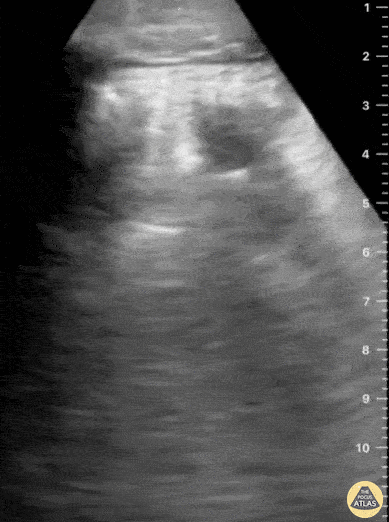

In this patient with history of blunt chest trauma, lung ultrasound reveals a focal area of B-lines as well as a hypoechoic wedge shaped subpleural consolidation. These findings are consistent with pulmonary contusion and can be identified early in the course of a patient’s care. This contrasts with hours-to-short-days that it often takes to fully appreciate the evolution of pulmonary contusion on chest X-ray. Aaron Inouye, PA-C, North Canyon Medical Center @PAintheED